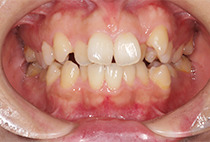

出っ歯と前歯のガタつきにお悩みだった20代女性の症例です。

前歯のガタガタ、中心のずれ、顎のずれ、外科矯正は避けたい

叢生、左右非対称咬合

矯正治療2年6ヶ月